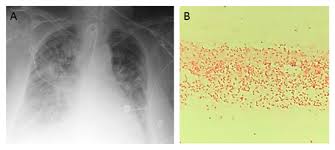

An Atypical Case Of Raoultella Planticola Urinary Tract Infection Infectious Diseases

An Atypical Case Of Raoultella Planticola Urinary Tract Infection Infectious Diseases from www.consultant360.com

Pdf Isolation Of Raoultella Planticola From Clinical Specimens In Hilla City Iraq Alaa Al Charrakh Academia Edu

Pdf Isolation Of Raoultella Planticola From Clinical Specimens In Hilla City Iraq Alaa Al Charrakh Academia Edu from 0.academia-photos.com